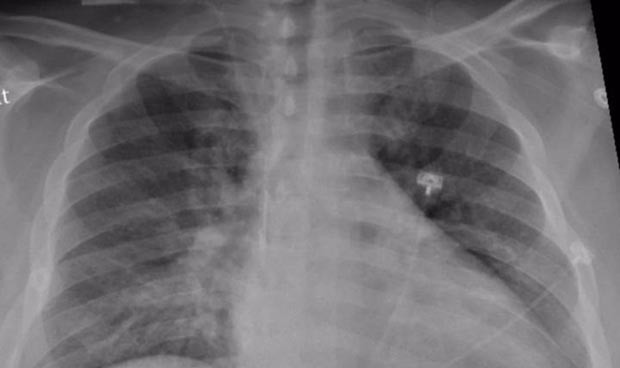

La radiografía de tórax de un paciente positivo de Covid que muestra una neumonía en la parte inferior.